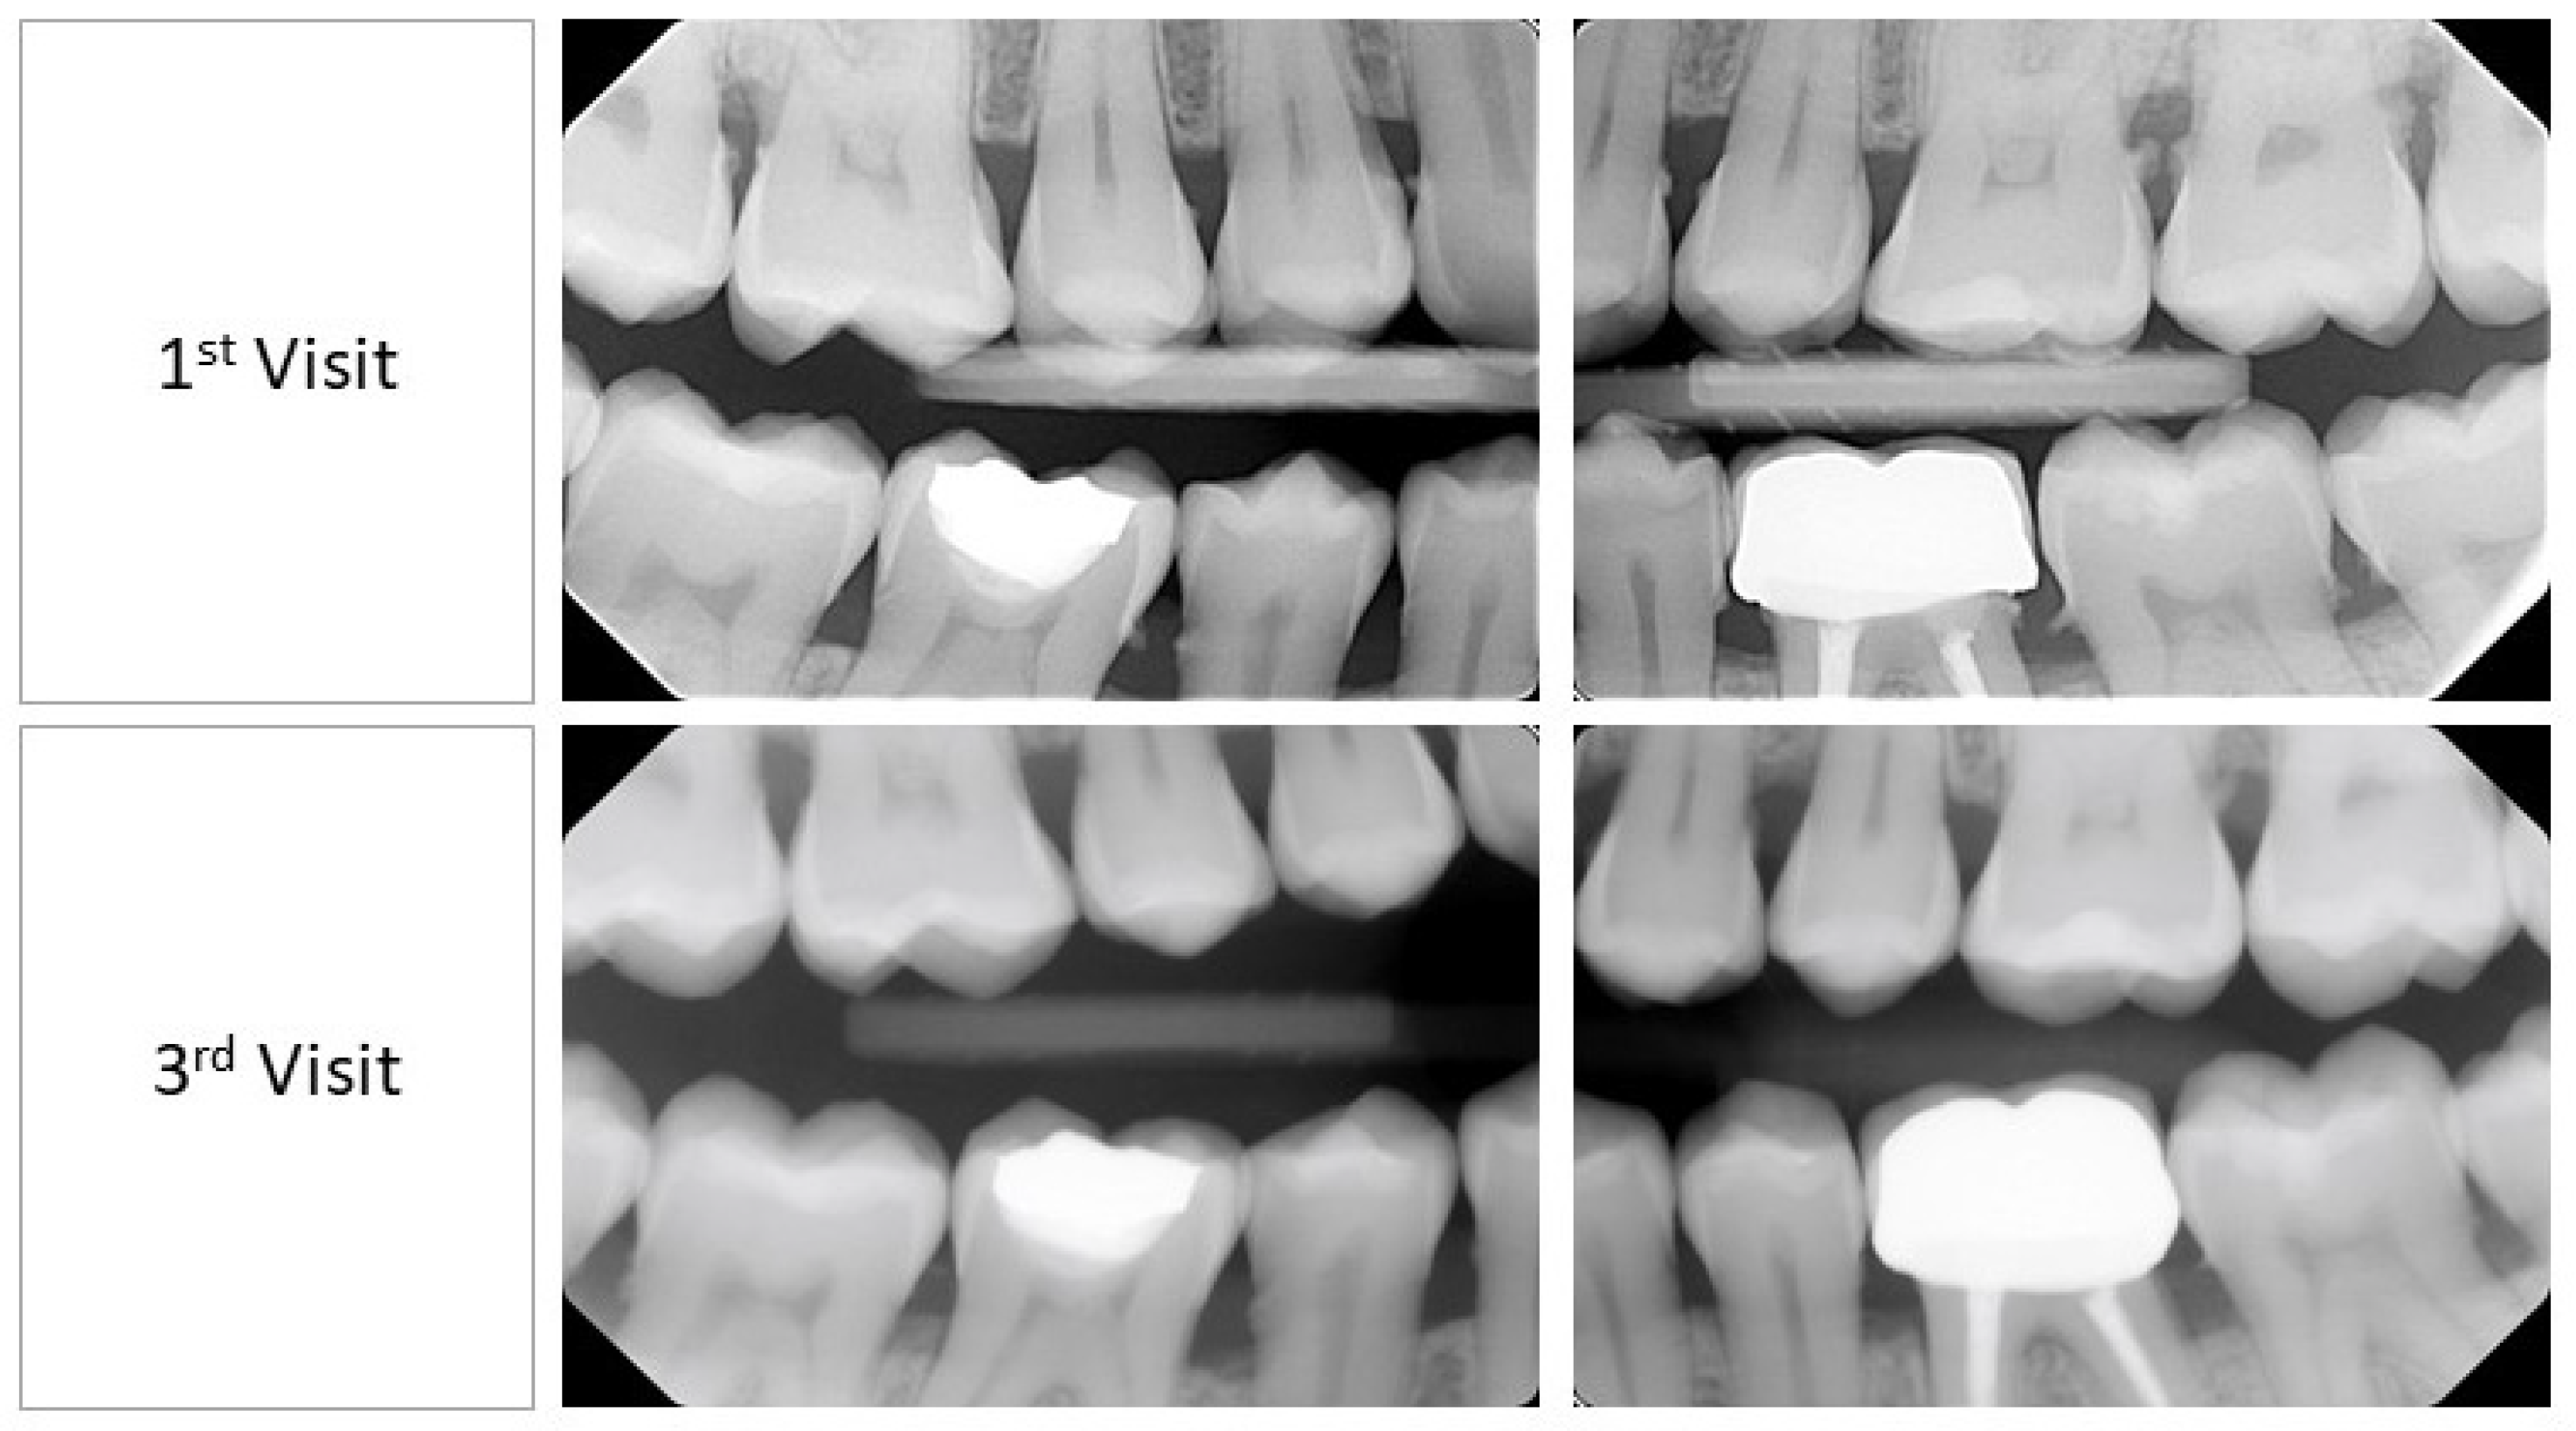

A clinical examination revealed interdental papilla and marginal gingival erythema (color), soft and spongy consistency, loss of stippling texture, and a generalized rolled gingival margin (Figure 1). This provided us with a wide view of the patient’s clinical gingival health including papilla, gingival margin, and gingival consistency. An in-depth view presented using a bitewing radiographic examination revealed generalized bone loss as a result of papillary contours (Figure 2). The dental indices utilized in this case study were the gingival index by Loe and Silness [15], plaque index by O’Leary et al. [16], and bleeding on probing (BOP) by Ainamo and Bay [17]. The examination at first appointment revealed the following: gingival index: 2; plaque index: 21%; and bleeding index: 14%. Hence, dental charting was utilized for a detailed illustration of each site’s conditions, which uncovered deep pockets in multiple sites (Figure 3).

Dental indices after 7 days from baseline revealed the following: gingival index: 2; plaque index: 50%; and bleeding index: 38%. On the other hand, after 14 days, the dental indices showed gingival index: 2; plaque index: 15%; and bleeding index: 9%. Intraoral conditions on the second and third appointments are shown in Figure 1 and Figure 2. It is worth noting that the visual analogue scale on the third appointment (after 14 days) reported no differences than what was reported in the first visit.

Figure 2. Bitewing radiographic examination at first visit: baseline and third visit: +14 days.